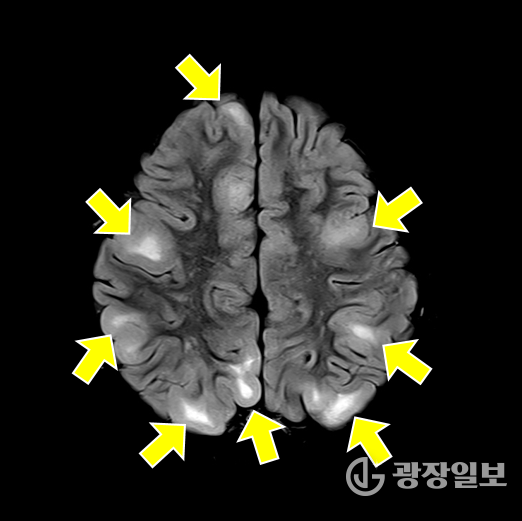

결절 경화증(tuberous sclerosis complex, TSC)은 종양억제유전자의 돌연변이로 인해 세포 증식이 조절되지 않고, 뇌·신장·피부·심장·폐 등 여러 장기에서 양성 종양이 발생하는 유전 희귀질환이다.

가장 흔한 증상인 뇌전증 발작과 피부의 혈관섬유종, 백반증을 비롯해 자폐스펙트럼장애, 인지장애, 신장 낭종, 폐세포 증식증 등 다양한 증상이 연령과 상관없이 나타나기 때문에 조기 진단과 장기적 관리가 필수적이다.